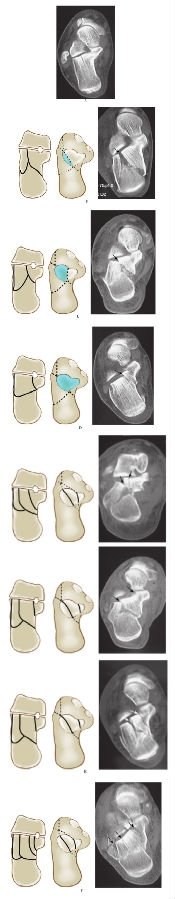

1、Sanders分型:

Sanders分型于1993年由Sanders提出,根据跟骨骨折的CT情况分型。这种分型主要反映了跟骨后关节面的损伤程度,对治疗方法的选择和判断预后有重要意义。此分型基于冠状位和轴位CT表现,在冠状面上选择跟骨后距下关节面最宽处,从外向内有两条线将其分为相等的三等部分,分别由A、B代表等分点,距下后关节面和载距突之间为C点,跟骨后距下关节面上的骨折线以其相对应的A、B、C点代表骨折线的位置。这样,就可能有四部分骨折块,三部分关节面骨折块和一部分载距突骨折块(图12)。

图12 Sanders分型

在冠状面上选择跟骨后距下关节面最宽处,从外向内有两条线将其分为相等的三等部分,分别由A、B代表等分点,距下后关节面和载距突之间为C点,跟骨后距下关节面上的骨折线以其相对应的A、B、C点代表骨折线的位置。这样,就可能有四部分骨折块,三部分关节面骨折块和一部分载距突骨折块根据后关节面骨折的情况,将跟骨关节内骨折分为四型:

Ⅰ型:无移位的关节内骨折(移位<2mm),不考虑后关节面骨折线的数量和位置。

Ⅱ型:跟骨后关节面为两部分骨折(即有一条骨折线两个骨折块),移位≥2mm,根据骨折线的位置又分为ⅡA、ⅡB和ⅡC型。

Ⅲ型:跟骨后关节面有两条骨折线三个骨折块,又分ⅢAB、ⅢBC及ⅢAC三个亚型。各亚型均有一中央塌陷骨折块。

Ⅳ型:跟骨后关节面为四部分骨折块及以上的移位骨折,包括严重的粉碎性骨折(图13)。

图13 跟骨关节内骨折的Sanders分型

A. Ⅰ型 无移位的关节内骨折

B. Ⅱ型 后关节面的两部分骨折,移位≥2mm:Ⅱa骨折线偏外侧

C. Ⅱb 后关节面的两部分骨折,骨折线偏内侧

D. Ⅱc 骨折线邻近载距突

E. Ⅲ型 后关节面的三部分骨折:Ⅲab,Ⅲac,Ⅲbc

F. Ⅳ型 后关节面四部分以上骨折